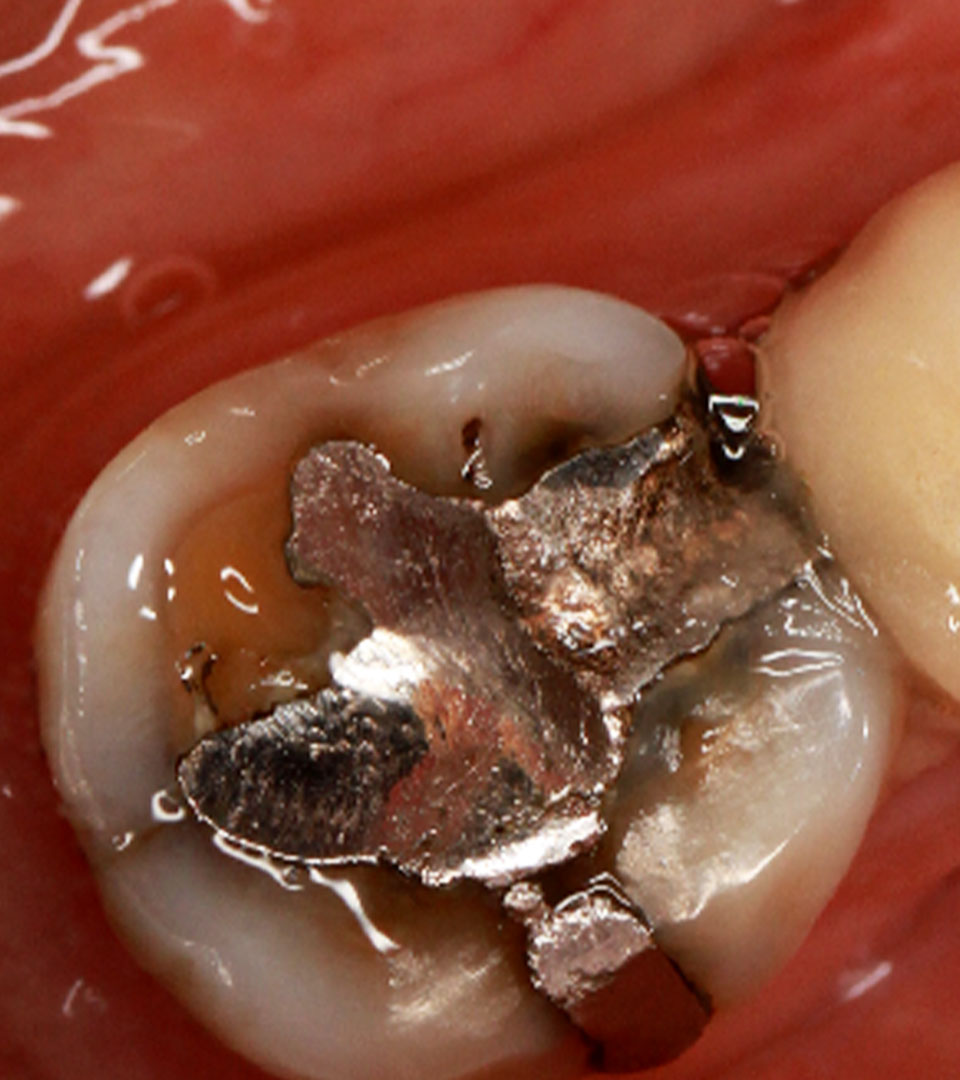

* 인레이 치료 치아 충치

레진 또는 인레이 치료를 받은 치아에 갈색 선이나 착색이 보인다면이미 2차 충치가 진행되고 있을 가능성이 높습니다. 표면에는 멀쩡해 보여도, 속에서는 이미 충치가 깊게 파고들었을 수 있습니다.